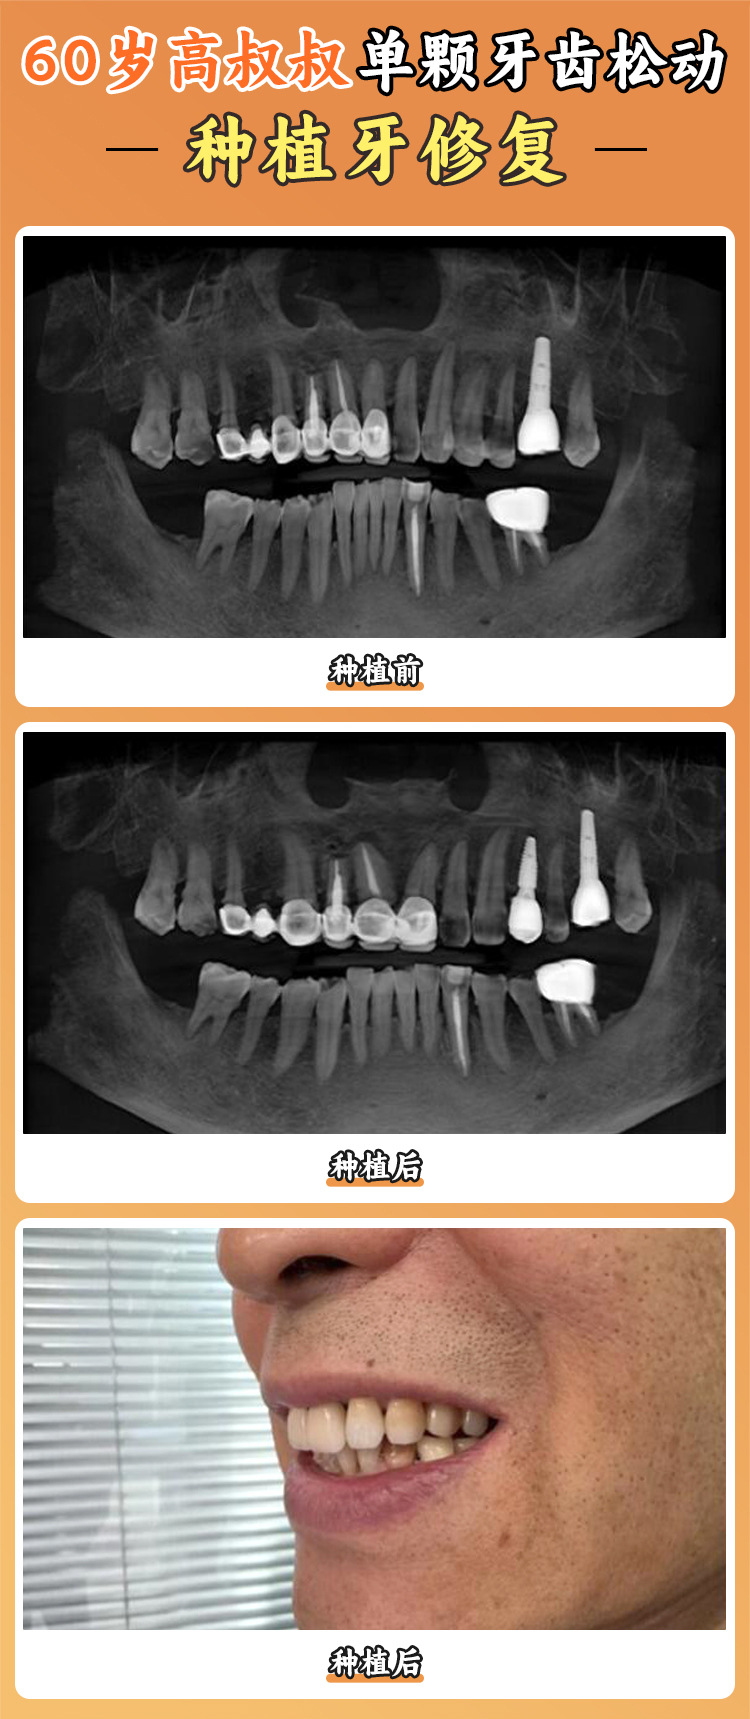

退伍軍人王先生在蘭州諾貝爾口腔做了all - on - 4即刻種植。他上牙缺失了14顆,僅剩下4顆殘根。整個手術(shù)用了1個小時,王先生無疼痛和其他不良感受。術(shù)后,講話、吃飯的困擾都得到了解決,吃蘋果、排骨都特別輕松,整個人精神狀態(tài)也變好了。